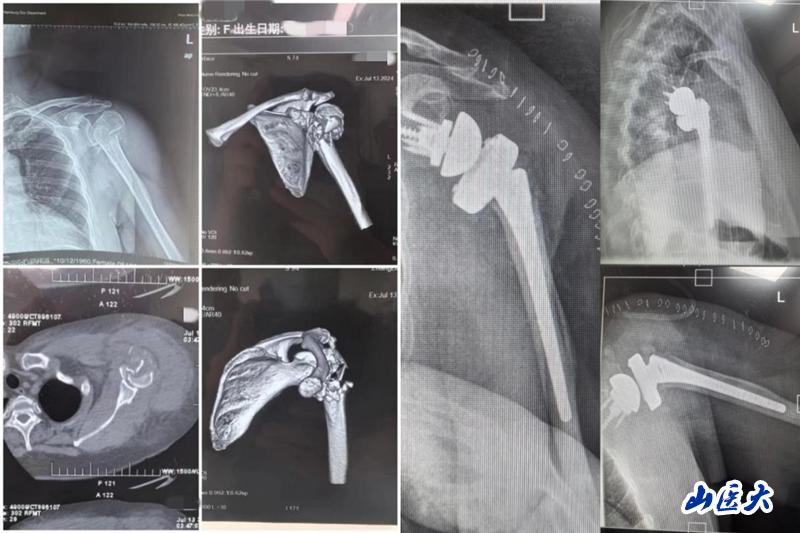

患者是一位63歲女性,主因車禍致左肩關節疼痛、腫脹伴活動受限就診,完善相關檢查結果示:左肱骨近端粉碎性骨折。栗樹偉副主任醫師團隊多次進行術前病例討論,綜合患者年齡較大、骨折類型為嚴重肱骨近端粉碎性骨折、肩關節功能嚴重受損等因素考慮,本著最大程度提高患者生活質量的醫療服務理念,決定為患者實施反向肩關節置換術。

經過積極充分的術前準備后,手術如期進行。由栗樹偉主刀,在骨科張晨醫師、麻醉科徐文會副主任醫師、手術室護士高君君和張文杰等團隊成員的通力配合下,憑借精準的解剖定位和精細的操作手法,最終順利完成這臺歷經3小時的手術。術中患者各項指標平穩,術后安返病房。

術后的精心護理對患者的恢復也至關重要,護理團隊耐心、細心、用心地護理和交流讓患者充分感受到關愛與溫暖。目前,患者術后拍片假體安置滿意,切口愈合佳,肩關節功能恢復良好,現已順利出院。